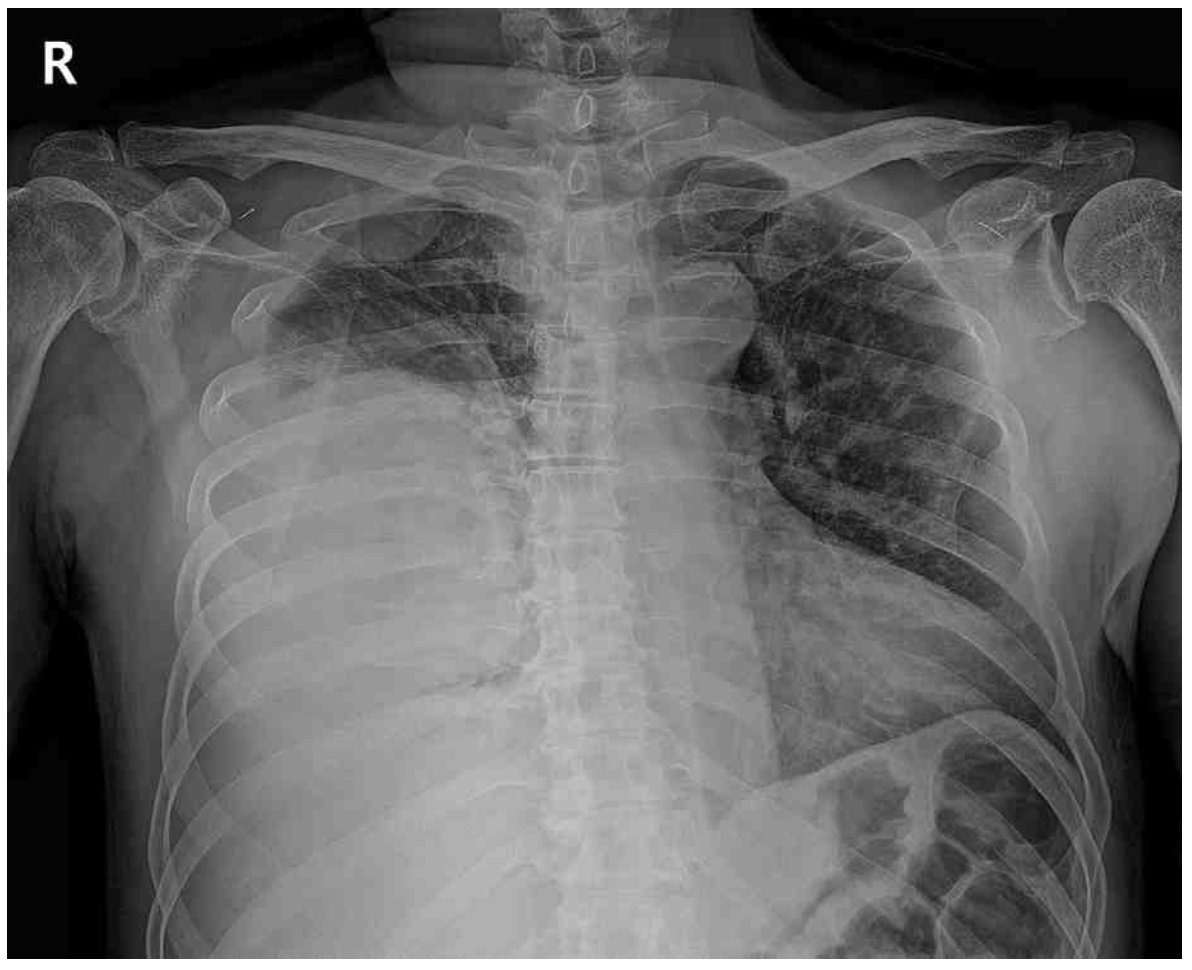

69세 남자가 1주 전부터 열이 나고 오한이 들어 병원에 왔다. 1일 전부터 가슴통증이 심해지고 숨이 찼다고 한다. 당뇨병으로 치료 중이고 비흡연자이다. 혈압 136/80 mmHg, 맥박 102회/분, 호흡 24회/분, 체온 38.6°C이다. 오른쪽 가슴에서 호흡음이 감소되어 들린다. 가슴 X선사진과 가슴 컴퓨터단층촬영 사진이다. 검사 결과는 다음과 같다. 검사는?

CXR: Rt. pleural effusion

• CXR상 우측 흉강의 pleural effusion을 관찰할 수 있으며 chest CT에서도 해당 부위의 loculated pleural effusion을 확인할 수 있다. 현재 발열, 빈맥, 빈호흡 및 CRP elevation, neutrophil-dominant leukocytosis 등으로 보아 세균성 감염이 원인으로 추정되며, 환자가 당뇨병으로 치료 중이라는 점에서 감염에 취약한 상태일 가능성을 배제할 수 없다.

• CXR 및 chest CT를 통해 흉수의 존재를 확인하였으므로 진단적 흉막천자를 통해 그 원인을 감별하여야 한다.